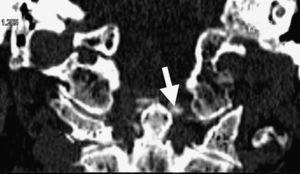

Axial skeleton affection due to chondrocalcinosis has been associated to calcium deposits in the intervertebral disc, the yellow ligament, the fact joints and even the sacroiliac joints. Calcification of the transverse ligament of the atlas (Figs. 1–3) is an infrequent manifestation and has been denominated the Crown Dens syndrome. It mostly constitutes an asymptomatic clinical picture but may be associated with episodes of acute cervical pain, stiffness and fever, with the added diagnostic difficulties of these cases.

We present the case of an 82-year-old woman who consulted us due to intense cervical pain which responded poorly to analgesics. She had a history of atrial fibrillation undergoing anticoagulation therapy, spondyloarthritis and radiologic chondrocalcinosis of the knees. Physical examination revealed spontaneous pain on the cervical spine, radiating to the occipital and mastoid regions, with stiffness and movement limitations due to pain, with no neurologic manifestations.

The Crowned Dens syndrome was described initially in 1985 by Bouvet et al.1,2 Diagnosis is based on the association of a compatible clinical picture and imaging findings, mainly calcium deposits in atlas-axis joint ligaments, visible on CT.3,4